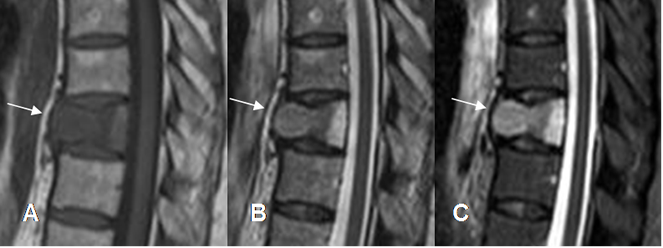

Fig 218. Fractura benigna.

A: Rx lateral, B: TAC reconstrucción sagital, C: RM sagital en T1 y D: RM sagital en STIR. Fractura vertebral hipointensa en T1 e hiperintensa en STIR, por evolución aguda. Sus bordes anterior y posterior son angulados, lo que sugiere origen benigno. (Flechas). Existe fragmento retropulsado.